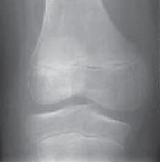

Chapter 35 Guided Growth to Correct Limb Deformity Peter M. Stevens DEFINITION Physiologic genu varum (before…

Chapter 30 Surgical Management of Blount’s Disease Eric D. Shirley and Richard S. Davidson DEFINITION Blount’…